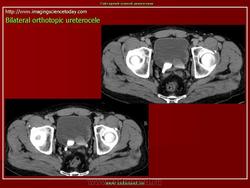

Уретероцеле

Приложения: